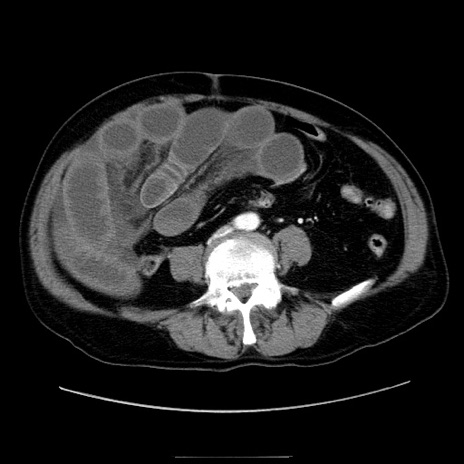

冠状断像

症例30(横断像)

【症例】80歳代男性

【主訴】臍周囲痛

【現病歴】約6時間前から臍下部痛が出現。次第に腹部膨隆・背部痛も生じてきたため来院。背部痛の場所は変化しない。

【既往歴】腎盂腎炎

【身体所見】意識清明、BT 36.3℃、BP  131/87mmHg、P 87bpm、SpO2 100%(RA)、臍周囲自発痛・圧痛あり、反跳痛なし、自発痛部位に一致して板状硬あり、腹部膨隆、腸雑音減弱、CVA tenderness両側陰性。

【データ】WBC 19600、CRP 0.33